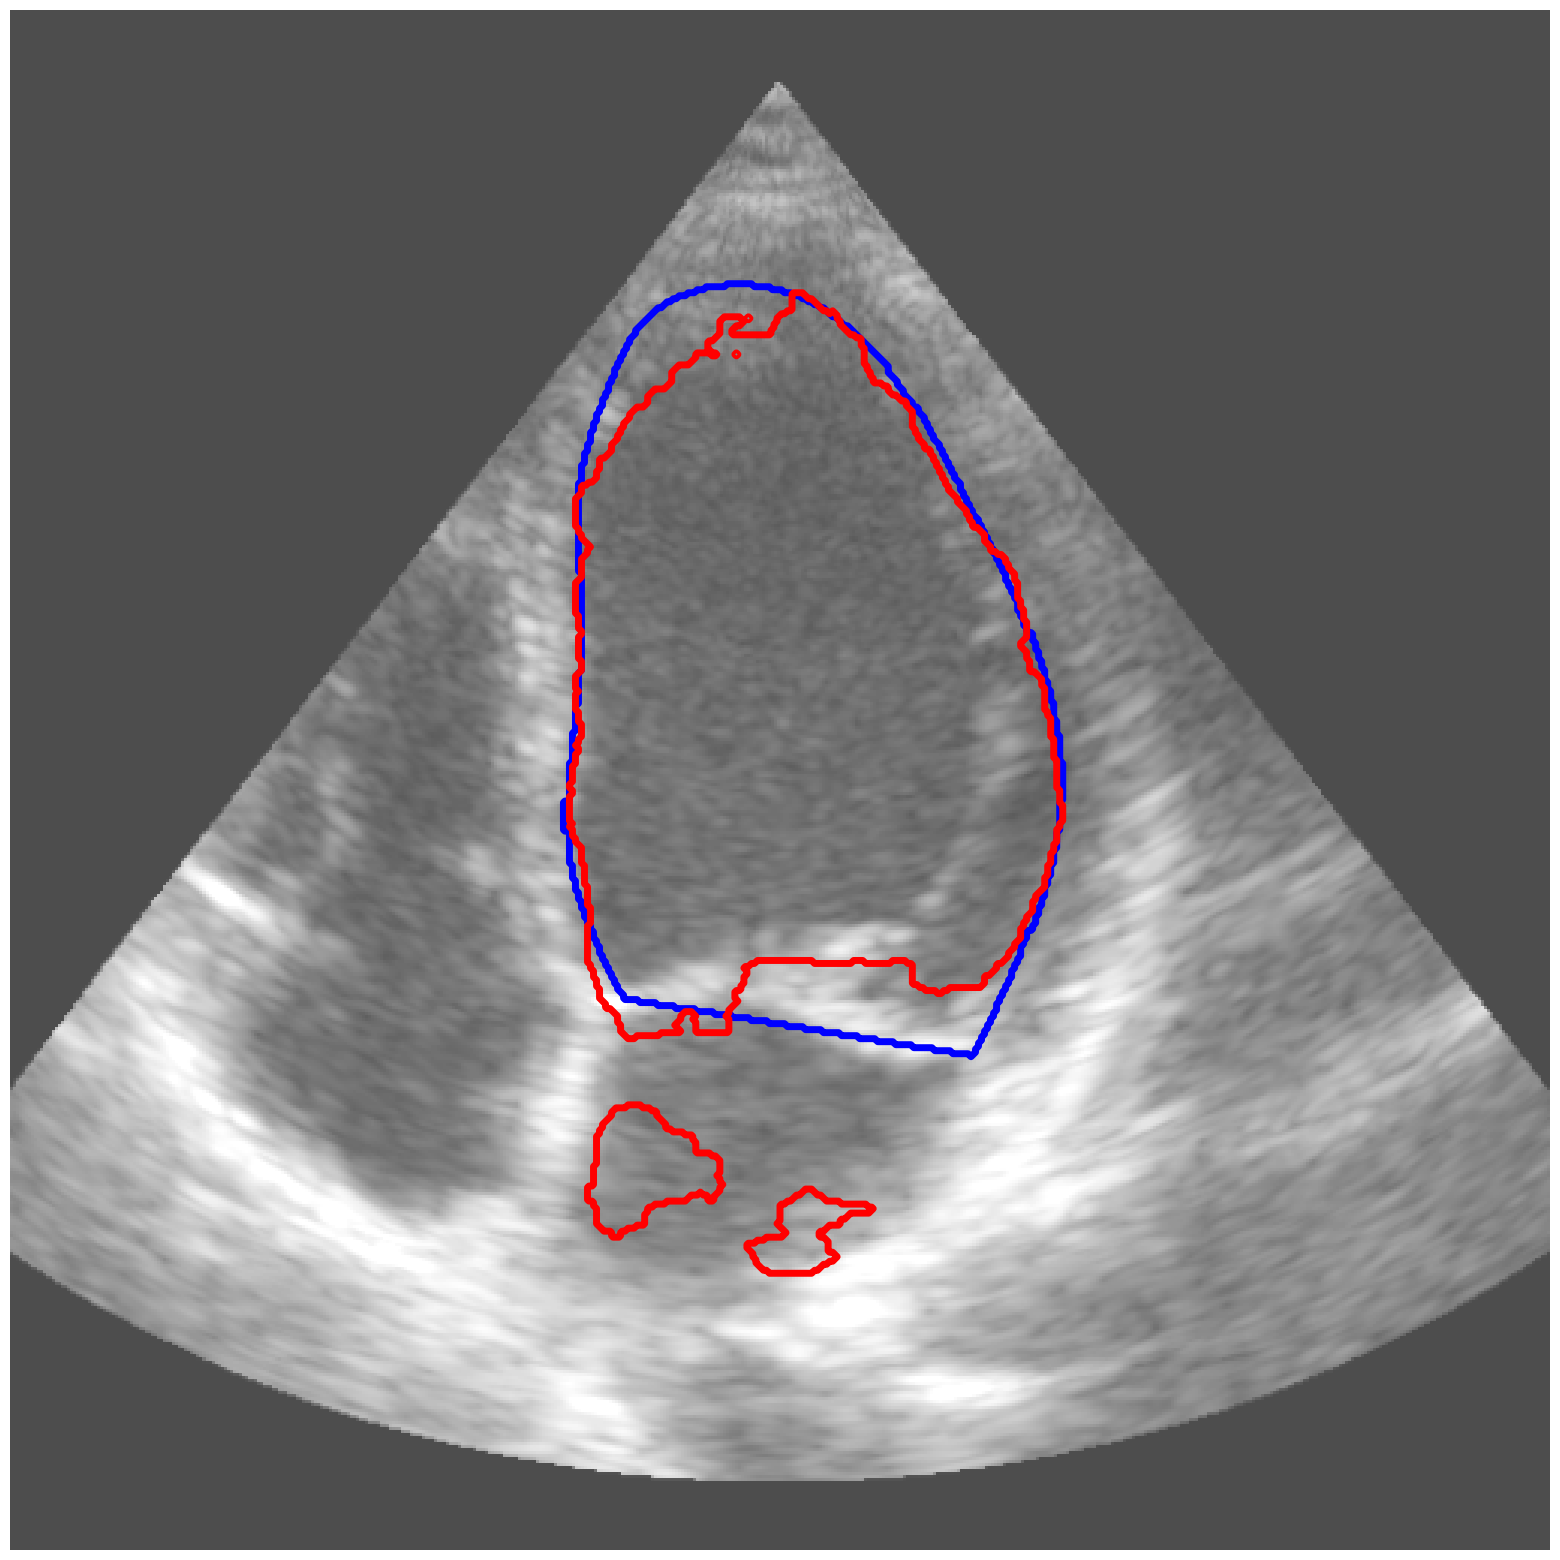

|

CAMUS |

![]() |

| (a) Original pred. | b) Consema | ——— c) Standard CRC ——— | ——— d) RW-CP (Ours) ——— | |||

Visually, we observe in Fig. 1 that RW-CP is able to produce prediction sets much closer to the ground-truth than standard CRC or Consema. Our approach is even able to remove small over-segmentated areas, whereas methods such as Consema can only increase the size of the prediction set, even when the segmentation model produced false positives.

We hypothesize that the performance of RW-CP stems from its pre-processing step on probabilities, which mitigates the overconfidence commonly observed in deep learning segmentation models [16]. Their raw softmax probabilities are often skewed towards either 0 or 1 (see Fig. 1.c). This overconfidence compresses the effective range of possible values for the empirical threshold used in Conformal Risk Control, making the final prediction mask extremely sensitive to small fluctuations in . On the contrary, by first applying a diffusion process, the pixel-wise probabilities become more varied and less polarized (as shown in Fig. 1.d). This broadened distribution stabilizes the empirical during calibration, leading to a more robust and tighter prediction set, which translates to better overall segmentation metrics